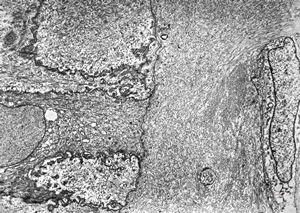

F,72y. | melanoblastoma oculi